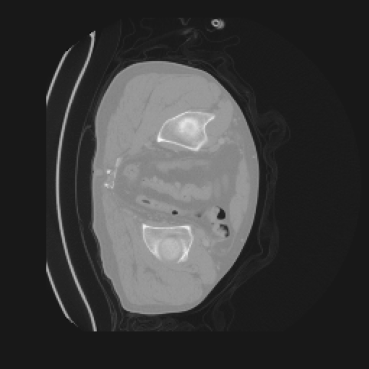

4.3 VQ-GAN Can Effectively Compress Images in a Perceptual Manner

Our method builds upon the assumption that the latent space learned by the VQ-GAN can effectively compress spatial information while preserving its correspondence with the pixel space. This property ensures that conducting semantic diffusion within the latent space remains meaningful and consistent with the original image structure.

In our approach, we employ a compression factor of 4 to encode 3D medical images into the latent space. This level of compression reduces the spatial resolution of the original image (e.g., from 256×256 to 64×64 per slice), while still preserving the essential anatomical structures and semantic content. The latent representation at this scale offers a favorable trade-off between dimensionality reduction and semantic fidelity. Specifically, although fine-grained textures are simplified, key structural patterns (e.g., organ boundaries, lesion shapes) remain visually distinguishable and semantically coherent. As the compression rate increases, the latent representations become progressively more abstract. With lower compression (e.g., 2× or 4×), the latent features preserve key anatomical structures and spatial layouts, making them beneficial for our semantic image synthesis task in latent space, as the model can operate on compressed representations that retain sufficient semantic information without being overwhelmed by high-frequency noise. In contrast, higher compression rates (e.g., 8× or above) lead to a loss of fine-grained details and reduced semantic fidelity. The choice of a 4× compression thus ensures that the latent features are compact and meaningful, facilitating effective conditional generation while significantly reducing computational overhead. We therefore adopt a 4× compression as a compromise between computational efficiency and semantic preservation. The corresponding 2D slices in image space and latent space are shown in Figure 7.

Most bits in a digital medical image represent imperceptible or semantically irrelevant details [7]. To address this, we employ a VQ-GAN as a perceptual compressor that transforms high-resolution medical images into a compact latent space while preserving essential semantic structures. This compressed representation significantly reduces spatial dimensionality, thereby lowering the computational and memory complexity of subsequent generative modeling. Additionally, operating in the perceptually meaningful latent space enables the latent diffusion model to focus on high-level semantic generation, leading to improved synthesis quality. Finally, the decoder reconstructs high-resolution images from the latent space. By separating the compression and generation stages, our framework enables both computationally efficient and semantically faithful 3D medical image synthesis.